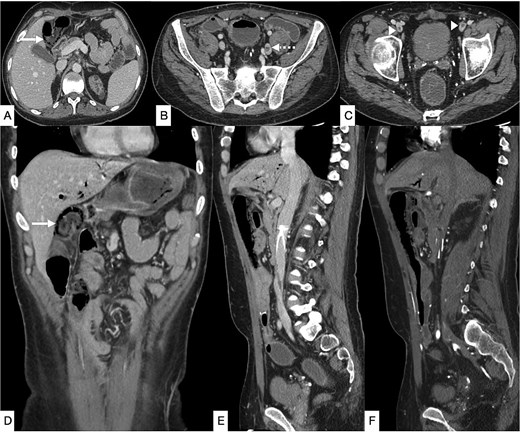

Contrast-enhanced computed tomography (CT) of the abdomen demonstrated long-segment ischemia extending from the transverse to descending colon, characterized by wall thickening, mucosal hypoenhancement, and pericolic fat stranding. A non-occlusive thrombus was noted in the IVC (Fig. 1). Review of prior CT angiography, performed several months earlier for gastrointestinal bleeding, had shown features of colonic angiodysplasia, including mucosal hyperenhancement, early venous filling, and serpiginous submucosal vessels (Fig. 2).

Contrast-enhanced CT of the abdomen and pelvis in axial (A, B) and coronal (C–E) planes showing a long segment of pneumatosis intestinalis involving the remaining descending colon, transverse colon, and proximal sigmoid colon, with suspicion of bowel perforation (bold arrow). Pneumobilia is present (dashed arrow). An eccentric intraluminal hypodensity within the IVC (arrowhead) is consistent with a non-occlusive thrombus, with a possible thrombus in the inferior mesenteric vein.